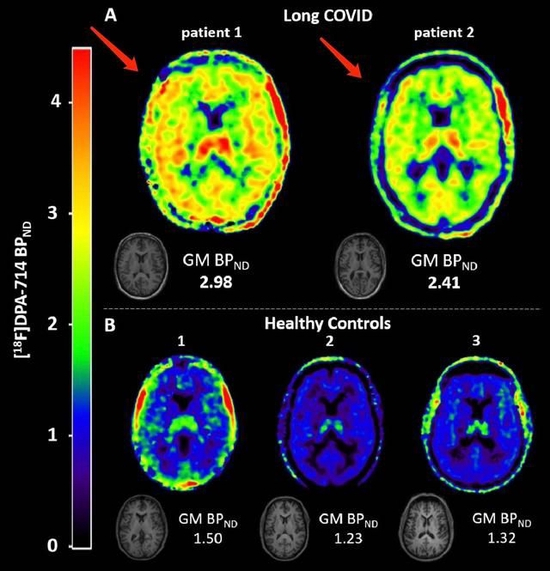

该研究采用了正电子发射断层扫描(PET)观察了长新冠患者大脑中的[18F]DPA-714水平,从而评估了患者大脑神经中小胶质细胞激活炎症。[18F]DPA-714是PET示踪剂,是一种高亲和力转运体蛋白(TSPO,一种在脑中活化的小胶质细胞和巨噬细胞中表达的线粒体外膜蛋白,作为神经炎症标志物)配体。[18F]DPA-714可用于评估各种神经炎症模型和脑肿瘤模型中的炎症特异性成像。

研究者对2名长新冠患者进行了动脉血样动态60分钟[18F]DPA-714 PET扫描。为了评估示踪剂代谢,研究者将两名长新冠患者血液中的[18F]DPA-714代谢物与所有其他可用受试者的血液中的代谢物进行了比较。他们评估了全血中的活性浓度,校正了来自动脉血样本的注射活性和示踪母体分数。

研究发现,长新冠患者1在所有脑区的[18F]DPA-714结合严重升高。其2T4k_VB模型获得的全脑灰质定量BPND(=k3/k4)相对于健康对照受试者平均增加了121%。长新冠患者2的[18F]DPA-714结合也升高了,从2T4k_VB模型获得的全脑灰质BPND(=k3/k4)相对于健康对照受试者平均增加79%。